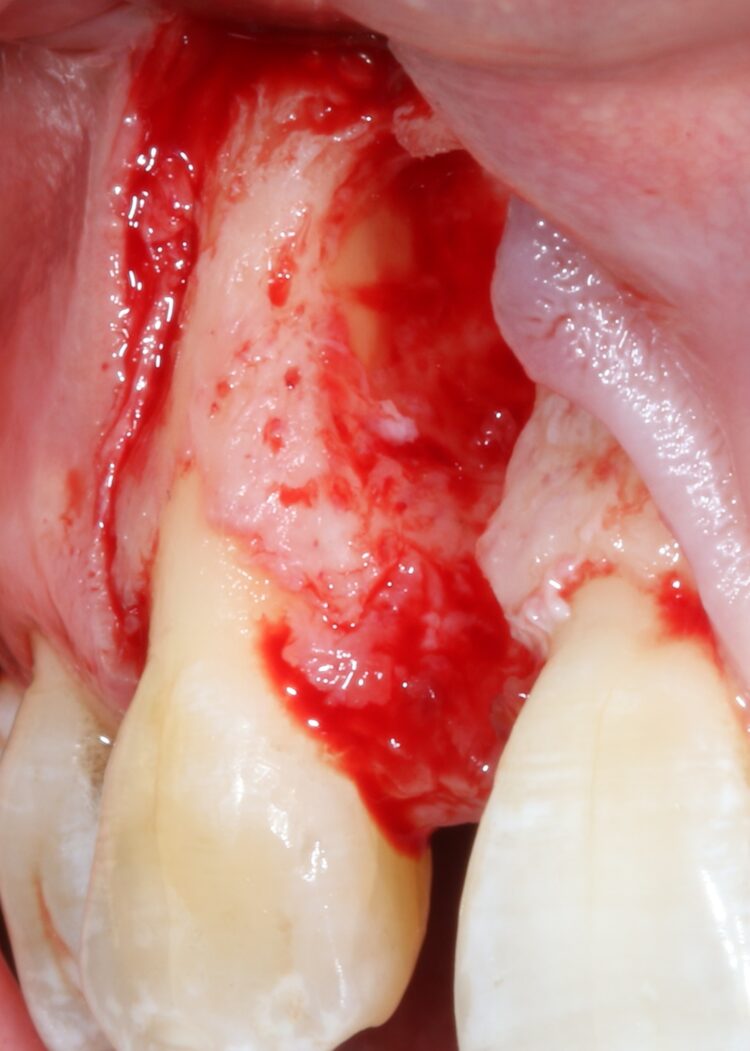

The second surgery involved a palatal crestal incision and a full thickness flap elevation revealing good turnover of bone graft into host bone. A bone level implant was placed in an appropriate three-dimensional position completely surrounded by new bone and no additional bone grafting was required. A 4mm healing cap was placed.

A free gingival graft was taken from the palate below the upper right molar teeth and the epithelium was removed on the surgical table. The connective tissue strip of graft was then placed on top of the healing cap (and suspended over the healing cap) and secured to the palatal flap with 6.0 PGA Resorba Sutures. Finally, the buccal flap was closed with complete primary intention wound healing using 6.0 Prolene.